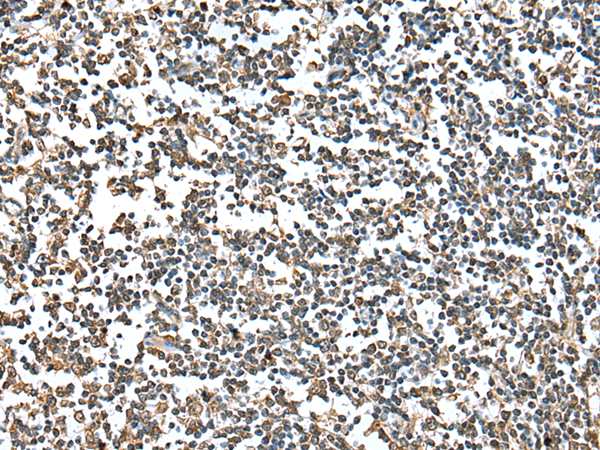

IHC positive control: |

Human gastric cancer and human tonsil |

IHC Recommend dilution: |

25-100 |